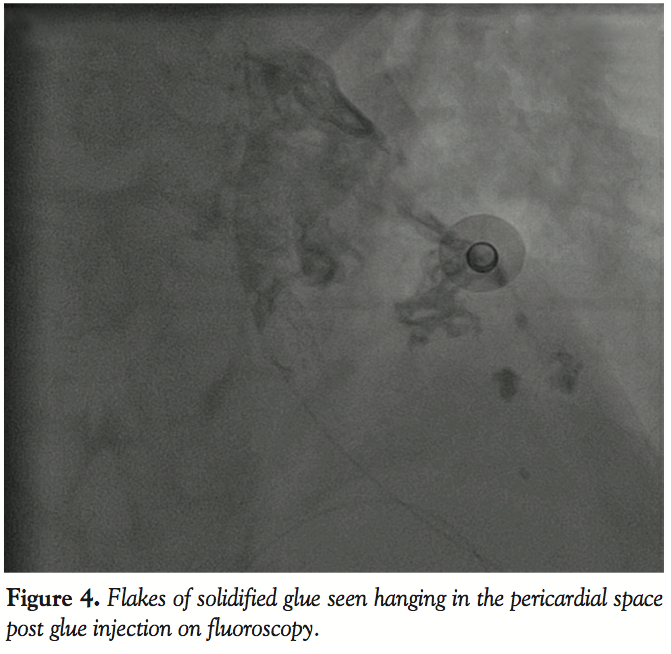

We first ensured that maximum possible blood had been drained out of the pericardial space (through the in situ catheter) so that the two layers of the pericardium were as close together as possible. The pigtail catheter was then exchanged for an infant feeding tube passed in through the 7 Fr vascular sheath in place. Injection of sterile glue was then made through the infant feeding tube into the pericardial space. Each injection contained 0.3 mL of sterile synthetic glue (Histoacryl, Braun Inc.) diluted with 0.3 mL Lipiodol solution with a prior dextrose flush of the system so as to prevent setting of the glue anywhere in transit (Figure 4). A total of 5 such injections were performed. Following this, the patient stabilized and hemodynamics improved rapidly. Over the next 24 hours, serial echocardiography revealed no re-accumulation of pericardial fluid. The intrapericardial sheath was removed 24 hours later and the patient was closely monitored for the next 48 hours and subsequently discharged in a stable condition.

In our patient, because the stented site included the ostia of both the LAD and left CX, and there was no obvious angiographic leak, the use of covered stents or coil embolization was precluded. We then resorted to intrapericardial glue injection as a last resort with a view to seal the two layers of the pericardium, which would possibly contain any fresh leak by obliterating the space between the two pericardial layers as a result of glue adhesions within the space. Since the synthetic glue Histoacryl sets as soon as it comes in contact with sodium ions in tissue fluid, it was essential to pre-flush the entire system with dextrose solution while injecting into the pericardial space. Glue should be injected rapidly so that it does not come in contact with blood anywhere in transit, else it would set on the way itself. Mixing with Lipiodol helps keep track of the glue passage into the target site, since the glue particles themselves are otherwise radiolucent.